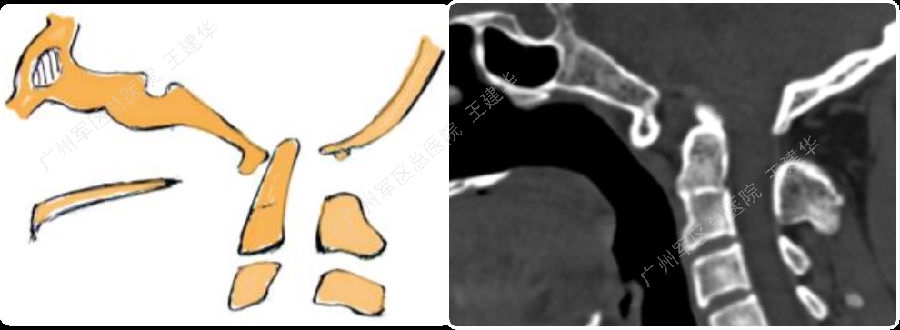

三维CT显示患者合并寰枕融合及C2/3融合,颅底凹陷

本例患者手术过程

手术前后对比

手术后2年复查的CT,显示侧块关节已经完全融合